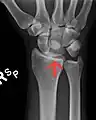

![]() Left hand anterior view (palmar view). Lunate bone shown in red. | |

The lunate bone (semilunar bone) is a carpal bone in the human hand. It is distinguished by its deep concavity and crescentic outline. It is situated in the center of the proximal row carpal bones, which lie between the ulna and radius and the hand. The lunate carpal bone is situated between the lateral scaphoid bone and medial triquetral bone.

The lunate is a crescent-shaped carpal bone found within the hand. The lunate is found within the proximal row of carpal bones. Proximally, it abuts the radius. Laterally, it articulates with the scaphoid bone, medially with the triquetral bone, and distally with the capitate bone. The lunate also articulates on its distal and medial surface with the hamate bone.[2]: 708 [3]

The proximal surface of the lunate bone is smooth and convex, articulating with the radius. The lateral surface is flat and narrow, with a crescentic facet for articulation with the scaphoid bone. The medial surface possesses a smooth and quadrilateral facet for articulation with the triquetral bone. The palmar surface is rough, as is the dorsal surface. The dorsal surface is broad and rounded. The distal surface of the bone is deep and concave.[4]